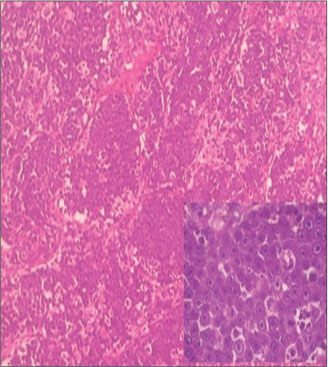

Resection of the mass was done. Intraoperatively tumor was well circumscribed, not involving the optic nerve. Histopathological examination showed bits of tumor tissue showing diffuse dense monomorphous proliferation of lymphoid cells, infiltrating in the orbital soft tissue and muscle, and tumor cells were medium-sized lymphoid cells with thin nuclear membrane, delicate chromatin, indistinct nucleoli, brisk mitoses, and scant cytoplasm. On immunohistochemistry, tumor cells were negative for desmin, mic2, MPO, and synaptophysin and positive for LCA, CD20 and Tdt [Figure 6].

|?Figure. 6? A Sheets of tumor cells infiltrating into orbital soft tissue and muscle, medium-sized lymphoid cells with thin nuclear membrane, delicate chromatin, indistinct nucleoli, brisk mitoses, scant cytoplasm ? Precursor B LL, (H and E, ?100), IHC: LCA, CD20, and Tdt- Positive|

Final diagnosis?Primary orbital precursor B-cell lymphoblastic lymphoma.

The patient was started with systemic chemotherapy and died during the treatment course.